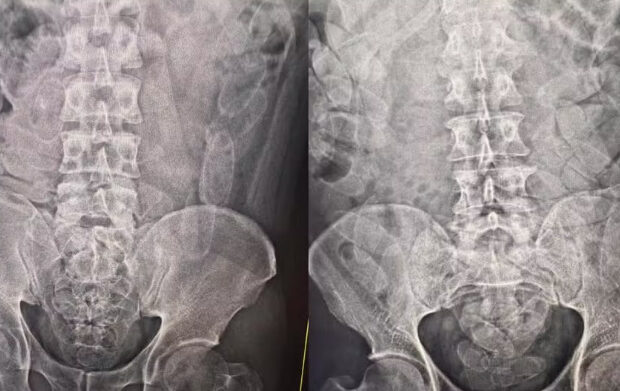

O trio foi levado até a Santa Casa de Corumbá, onde exames médicos confirmaram que eles haviam ingerido cerca de 100 cápsulas de cocaína, totalizando aproximadamente 3,5 quilos da droga.